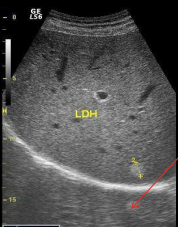

<p>En la imagen ves dos estructuras redondas dentro de un rectángulo y marcadas con flecha amarilla. Qué aspecto ecográfico tienen respecto del parénquima del bazo marcado con flecha roja</p>

En la imagen ves dos estructuras redondas dentro de un rectángulo y marcadas con flecha amarilla. Qué aspecto ecográfico tienen respecto del parénquima del bazo marcado con flecha roja

Isoecogénicas